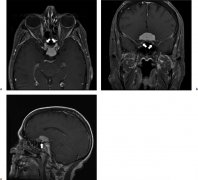

> 鞍结节脑膜瘤

鞍结节脑膜瘤是属于大手术吗?

鞍结节脑膜瘤占脑膜瘤的4-10%,并且几乎普遍存在不同程度的视力...